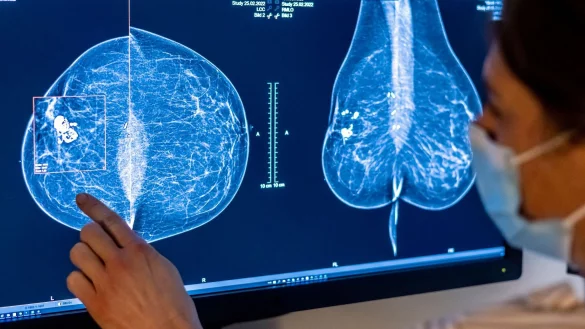

Brustkrebs-Früherkennung künftig bis 75 Jahre

Ausweitung der Brustkrebs-Früherkennung: Künftig dürfen Frauen bis zur Vollendung ihres 76. Lebensjahres an dem Screening teilnehmen. Das sieht eine novellierte Verordnung des Bundesumweltministeriums vor, die an heute in Kraft tritt. Zusätzlich rund 2,5 Millionen Frauen haben durch die Ausweitung Anspruch auf eine Teilnahme, wie der Gemeinsame Bundesausschuss mitteilte, das oberste Entscheidungsgremium über Leistungen der Krankenkassen im Gesundheitswesen.

Bislang war es Frauen nur bis 69 Jahren erlaubt, an den Röntgen-Untersuchungen teilzunehmen. Ab Juli können sich auch Frauen zwischen 70 und 75 zum Mammografie-Screening anmelden. Der Bundesausschuss hatte die Altersgrenze im vergangenen Jahr angehoben. Die nun erteilte Strahlenschutz-Zulassung sei die letzte Voraussetzung für das Inkrafttreten, so der Ausschuss. Frauen im Alter von 70 bis 75 könnten sich folglich ab 1. Juli bei den sogenannten Zentralen Stellen für einen Untersuchungstermin in einer wohnortnahen Screening-Einheit anmelden.

Umweltministerin Steffi Lemke (Grüne) sagte: «Durch die erweiterte Altersgrenze können künftig noch mehr Frauen zu den Untersuchungen gehen.» Das finde hoffentlich großen Anklang. «Brustkrebs-Früherkennung kann eine echte Lebensretterin sein.» Brustkrebs ist mit jährlich rund 70.000 Neuerkrankungen die häufigste Krebserkrankung bei Frauen in Deutschland. Seit 2009 wird Frauen zwischen 50 und 69 Jahren alle zwei Jahre eine Röntgen-Untersuchung zur Früherkennung angeboten.